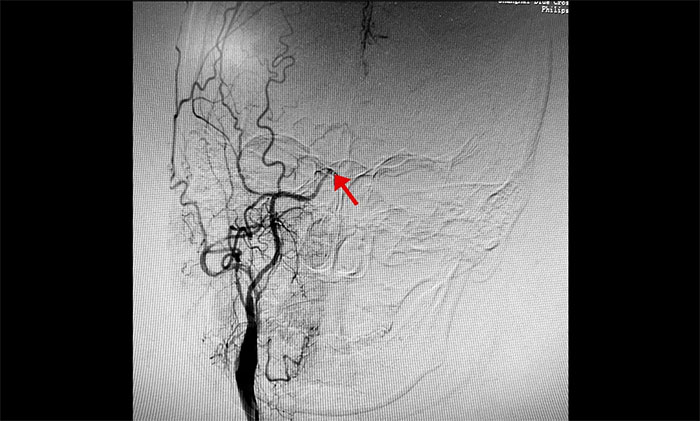

于耀宇主任为患者行DSA(数字减影血管造影)检查示:右侧颈内动脉末端闭塞,大脑中动脉M1段、大脑前动脉A1段不显影。左侧颈内动脉、大脑前动脉亦存在不同程度狭窄。颅底可见少量烟雾状血管形成,符合烟雾病特征。

▲ 右侧颈内动脉末端闭塞,少量烟雾状代偿血管形成